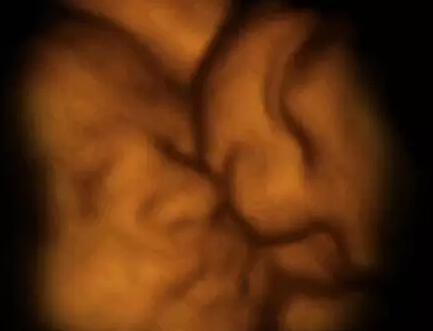

这张图见证了罕见的“双胎消失征”。图中居右的第3个胎盘是空的,这证明了多胞胎可能由于缺少营养而从子宫中消失。

在这里你甚至可以清晰辨认出画面前方这个双胞胎胎儿手上的根血管。